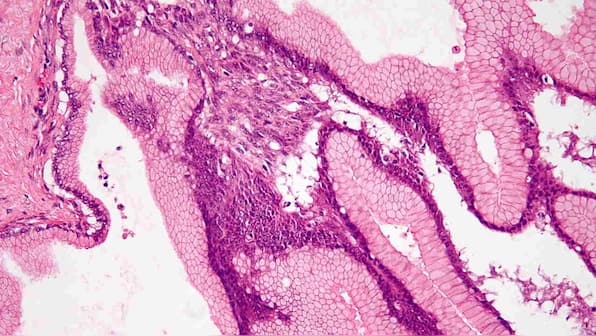

Tumor shrinkage

“Those patients whose tumour shrank with the olaparib, which was about a quarter of them, their tumour shrinkage was maintained for more than two years,” added Kindler, who presented the findings at the annual meeting of the American Society of Clinical Oncology. “The whole idea is… you can transform an otherwise deadly prognosis into a potentially chronic disease, at least for a while, and to keep it under control.” [caption id=“attachment_6745041” align=“alignnone” width=“1280”]Benign pancreatic mucinous cystic neoplasm. iamge crdt: Wikimedia Commons Representational image. Image credit: Wikimedia Commons[/caption] Suzanne Cole, an oncologist at Southwestern Medical Center who was not involved with the study said it represented a “huge step forward for patients with metastatic pancreatic cancer.” She added that now the effectiveness of the medication had been identified, it was important for clinicians to screen patients for the mutation to identify those who could benefit from the therapy. Kindler cited the case of a patient who watched his brother die from the disease before learning he himself had cancer. He was found to have the BRCA mutation and placed on the trial. “Every single time we do a CT scan, his tumour is smaller and smaller,” said Kindler. “He takes a pill twice a day, and two and a half years later, he’s still around. He’s leading a normal life.”